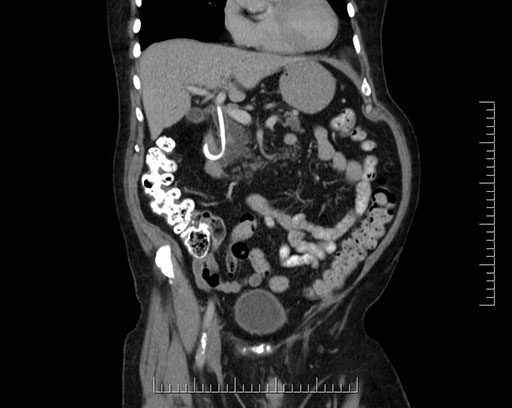

Coronal - stented